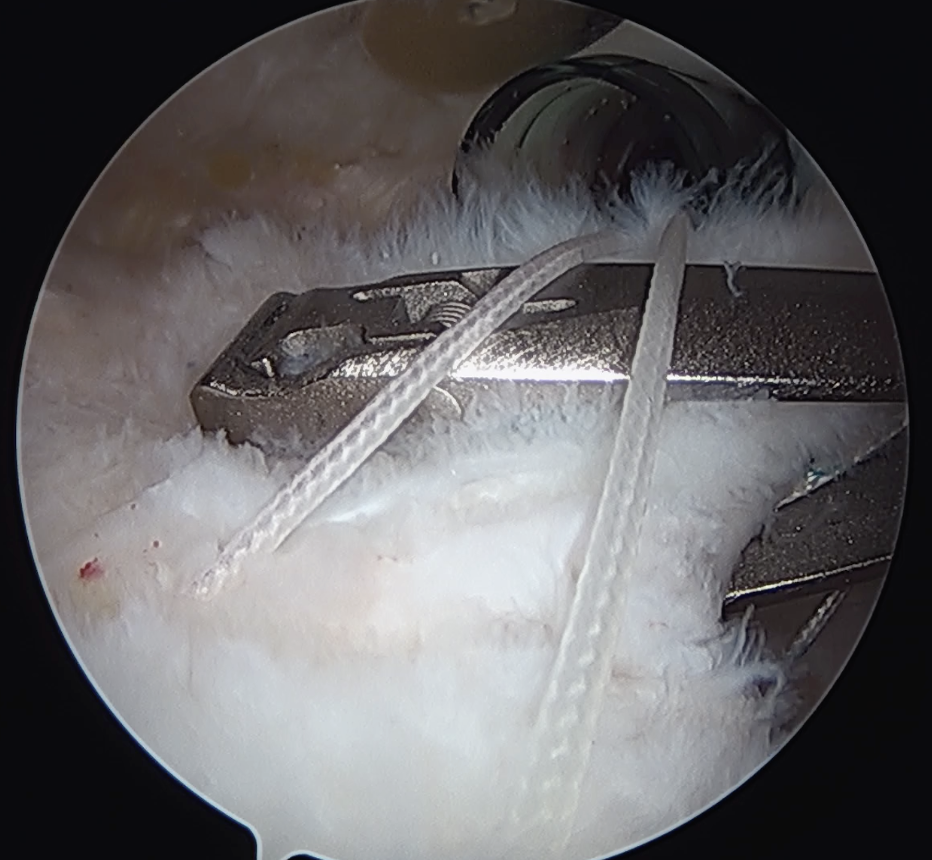

Trans-osseous equivalent / suture bridge

- cross sutures from medial row to lateral row

- increase contact between cuff and footprint

Double row / suture bridge

- use medial row sutures

- secure in knotless lateral row anchors